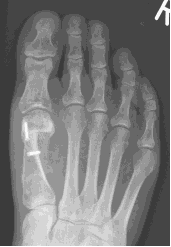

This is an osteotomy in the metatarsal head (transposition), the metatarsal head is moved to correct the deformity and fixated with a single screw. It is indicated for mild to moderate deformities. The choice to carry out a Scarf or a capital osteotomy will be made by your consultant.

This is a transposition osteotomy. It is normally indicated for mild to moderate deformities. The new position of the first metatarsal is maintained with two screws which enables stability.

This involves a fusion of the first metatarsal cuneiform joint, allowing the first metatarsal to be rotated back into a straight position. It is normally reserved for severe deformities. Once the corrected position has been obtained it is usually maintained with a plate and screws.